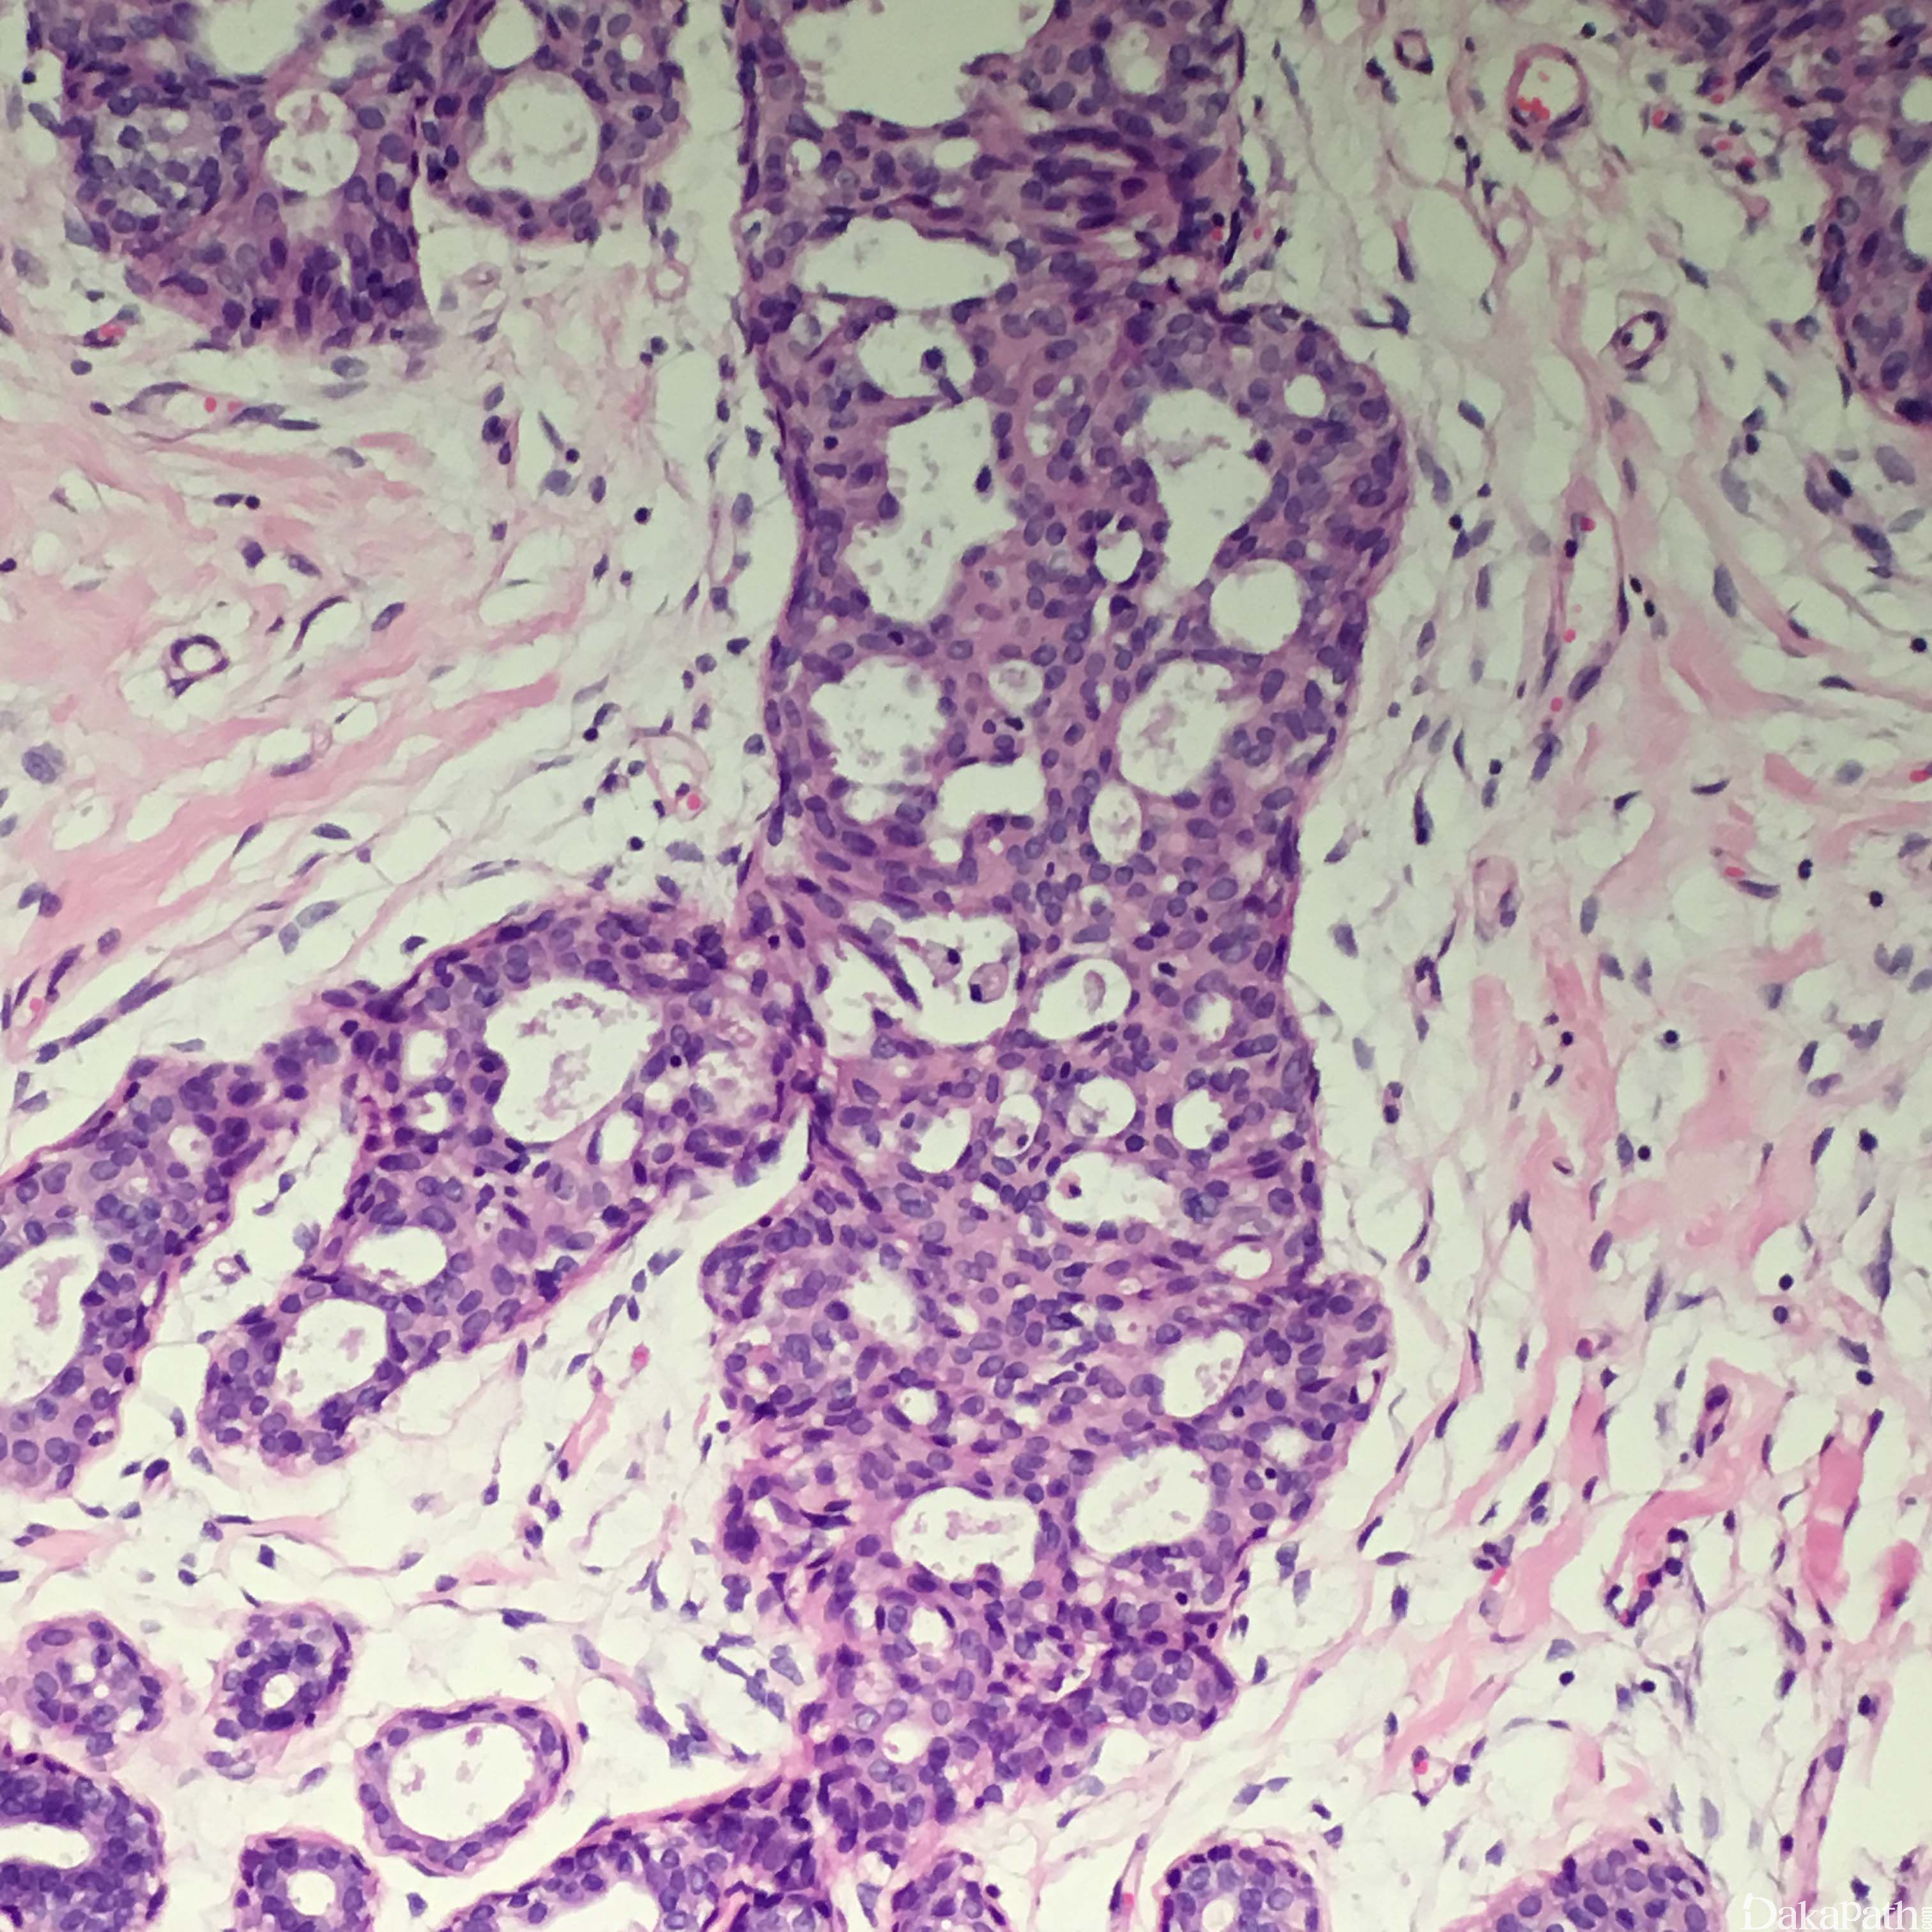

- 组织学结构特征:超过正常的乳腺的两层结构(肌上皮细胞和腺上皮细胞层),细胞杂乱的紧密增生。轻度增生是指 2-4 层增生的腺细胞,旺炽性增生是指大于 4 层增生的腺细胞,可以形成实性的、筛状的或微乳头结构。

- 实性型 UDH 表现细胞大小不等、形状各异,排列杂乱,可以出现导管周围裂隙样的空隙,肌上皮细胞层存在;

- 多孔型 UDH 表现为形成孔的腺腔不规则,腺腔大小和形状各异,经常裂隙样并出现在导管周围,和 ADH 及低级别 DCIS 中看到的圆形的、穿凿样的腺腔不同,不显示围绕腺腔的极向,排列杂乱、可以重叠;有些病例表现为梭形的腺细胞呈明显的流水样或旋涡状排列;

- 细胞学特征:可以有合体细胞特征,单个细胞的边界不清;细胞是多克隆增生,而不是单克隆增生;细胞大小、形状及核方向多样,常见核沟及核内包涵体;偶尔可以看到核分裂;有时可以看到中心坏死,特别是在增生非常旺盛的区域;可以存在大汗腺化生或透明细胞化生,而且存在这些化生往往说明是良性改变而不是 ADH 或 DCIS。